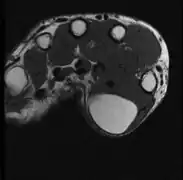

A physical exam is typically the easiest way to diagnose it. Rarely, a tissue biopsy or imaging may be required. The imaging modality of choice is magnetic resonance imaging (MRI) because it has superior sensitivity of distinguishing it from liposarcoma as well as mapping the surrounding anatomy.[22]

Medical ultrasonography of a lipoma in the thenar eminence: It is hyperechoic compared to adjacent muscle, and relatively well-defined, with miniature hyperechoic lines.[23] -

Ultrasonography of a liposarcoma for comparison: In this case a heterogeneous mass consisting of an upper hyperechoic portion, corresponding to lipomatous matrix, and areas of hypoechogenicity corresponding to nonlipomatous components.[24] -